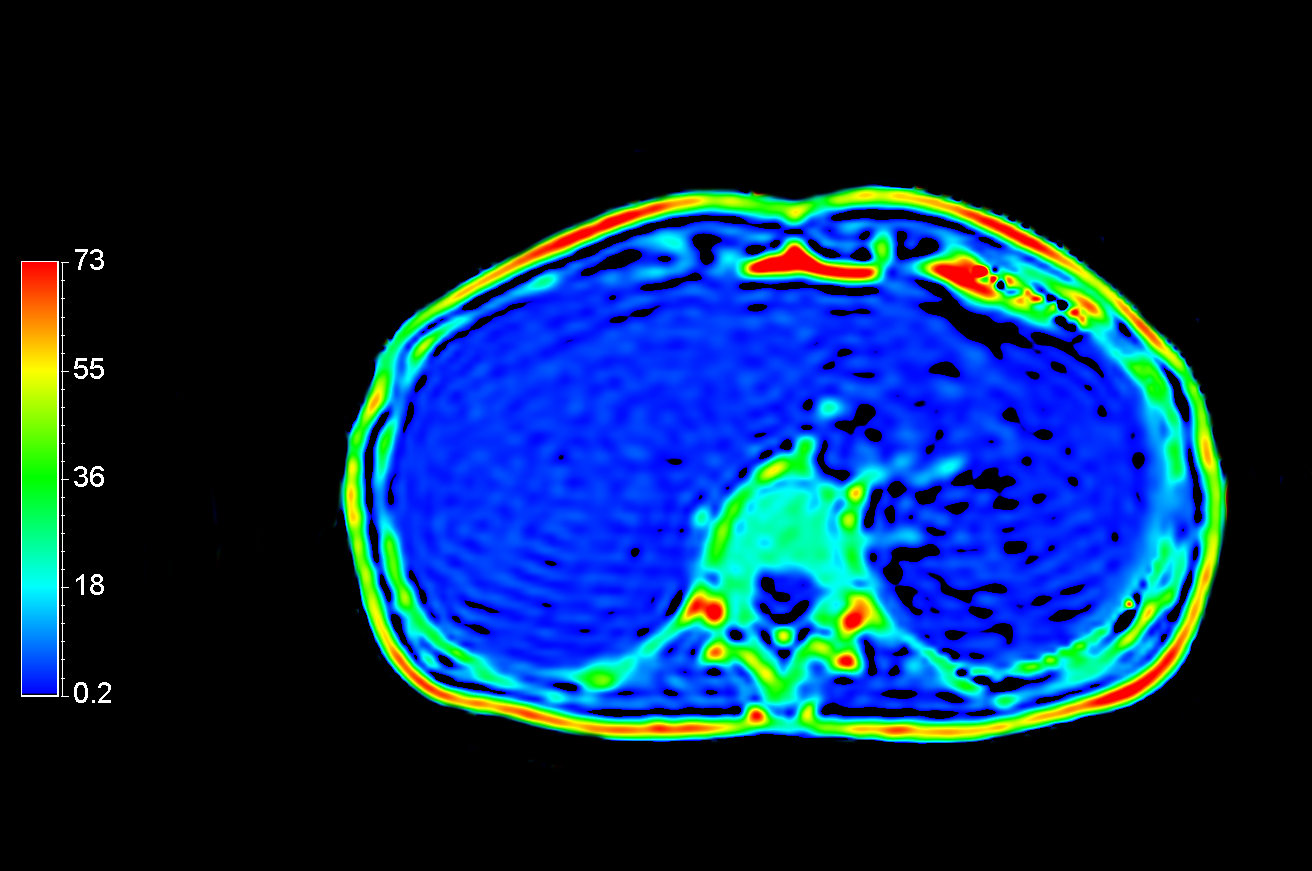

Axial DWI (ADC)